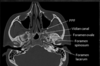

MDCT = one slide every rotation

How well did you know this?

1

Not at all

2

3

4

5

Perfectly

6

Q

components of CBCT

A

• xray generation

• xray detection

• image reconstruction